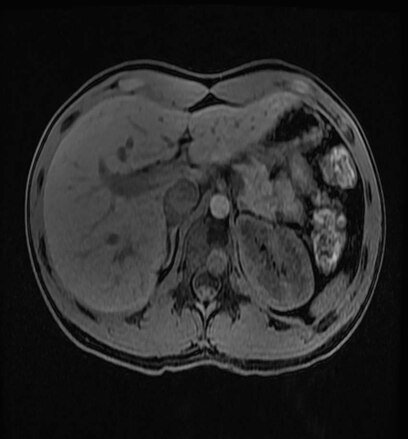

Non invasive procedures

3D Arterial Spin Labeling (3D ASL) delivers quantitative perfusion assessment-without radiation or the need for injection. IDEAL IQ delivers whole liver 3D coverage in a single breath-hold. It provides a non-invasive, quantitative assessment of triglyceride fat content in the liver that can aid in diagnosis. Further, our Inhance Suite delivers a set of non-contrast angiography solutions.